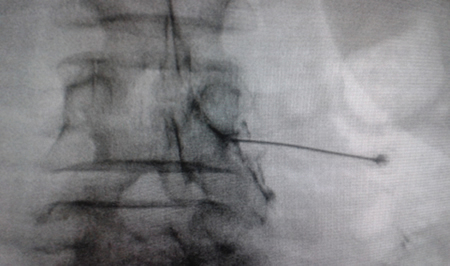

El acceso por vía transforaminal es el más utilizado (4). Se coloca al paciente en decúbito prono con una almohada a nivel abdominal para revertir la lordosis fisiológica. Las agujas o cánulas de radiofrecuencia que utilizamos con más frecuencia son de diámetro 20 o 22 G de 98 mm de largo con punta activa de 0,5 o 1 cm. Después de la asepsia con clorhexidina alcohólica y la colocación de campos estériles, se realizan enfoques radiológicos en incidencia anteroposterior, oblicuo y lateral. En incidencia anteroposterior y moviendo el arco en dirección cráneo caudal se borra el doble arco del borde inferior vertebral. En incidencia oblicua entre 20 y 30 grados ipsilateral al GRD a tratar, se visualizará la clásica imagen descrita como de “Scotty Dog”, que es resultado de acercar el macizo facetario y la apófisis espinosa al lado contralateral. El punto de entrada será entonces inmediatamente debajo del pedículo. Previa anestesia local con lidocaína al 1 %, la aguja se introducirá siguiendo una visión túnel y no se avanzará más allá de la mitad del pedículo en esta proyección con la finalidad de prevenir la lesión neural. En proyección lateral, se introducirá en el techo del neuroforamen

(Figuras 1 y 2) pero la localización final será determinada por la estimulación nerviosa sensitivo-motora. La estimulación sensitiva consiste en provocar parestesia o dolor en el territorio afectado con una estimulación entre 0,3-0,6 v. Durante la estimulación motora se pueden provocar fasciculaciones en el territorio afectado con un voltaje del doble al necesario para provocar las parestesias. Si se desea realizar una denervación intraganglionar, promulgada por algunos autores, la estimulación tanto sensorial como motora será positiva a menos de 0,3 v. Por tratarse de un procedimiento más doloroso, se aconseja administrar anestésicos locales después del estímulo doloroso y antes de realizar el tratamiento. La impedancia deberá mantenerse por debajo de 450 ohms, lo que se consigue infundiendo solución salina previa a la RF (4). La utilización de contraste constituye una buena práctica, ya que descarta la posición intravascular e intratecal de la cánula de radiofrecuencia.

Fig. 2. Imagen radiológica anteroposterior de una cánula de radiofrecuencia posicionada en neuroforamen L4-L5, en el llamado triángulo de seguridad, después de la inyección de contraste. Se observa un engrosamiento del radiculograma a nivel del techo del neuroforamen, que podría corresponder al ganglio de la raíz dorsal de L4